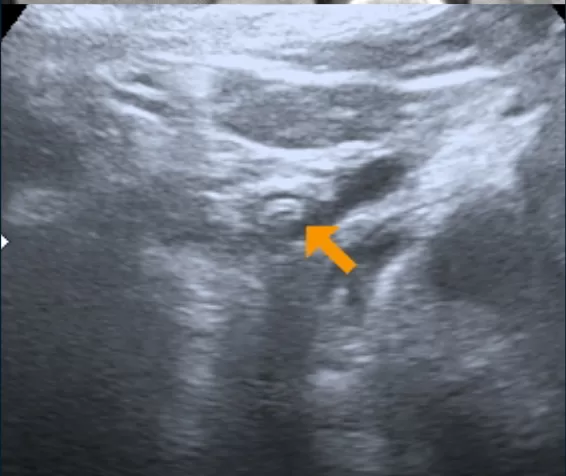

• Mulher de 40 anos

• Hipertensão, tabagismo, hipotireoidismo

• Dor abdominal difusa e intermitente, com duração de 3 meses

• Colecistectomia laparoscópica: 7 anos atrás

Cálculos biliares aderidos à parede duodenal

Colelitíase Livre na Cavidade Abdominal

-> Litíase aderida à parede duodenal: apenas alguns casos relatados na literatura